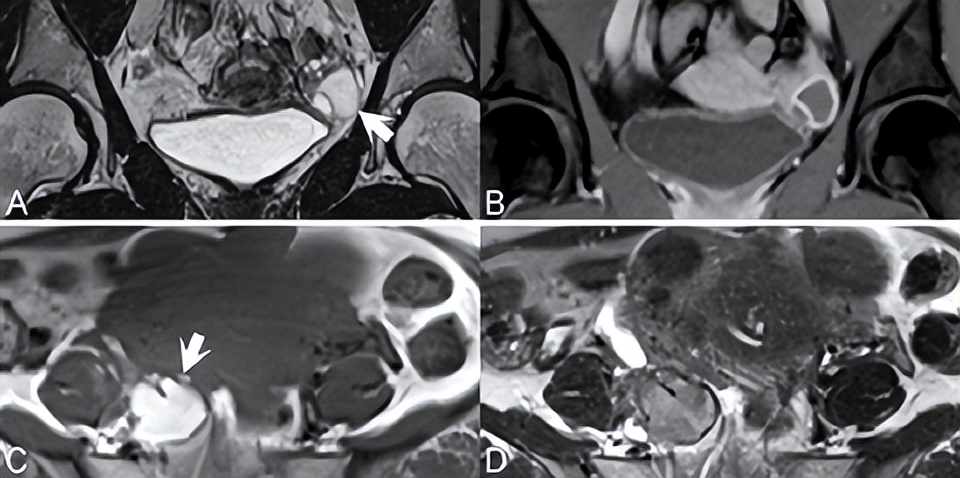

功能性滤泡性卵巢囊肿是常见的良性病变,通常表现为单房、薄壁病变,伴有水样信号(图76.1,轴位T2WI)。无功能性囊性病变是鉴别诊断因素,但由于肿瘤形成可能看起来相似,因此应在6周内通过超声重新评估新诊断的30 mm以上卵泡囊肿。滤泡囊肿的囊壁增强不如黄体囊肿。后者的壁通常也较厚,如图76.2A的冠状T2WI(白色箭头)所示,(B) CE T1WI显示管壁明显增强。

出血性黄体囊肿很常见,在图76.2C中示出,在轴位(C,白色箭头)T1和(D) T2WI上D分别为高信号和低信号。多囊卵巢综合征(PCOS)和卵巢过度刺激综合征中可见多个双侧囊肿。在多囊卵巢综合征中,根据定义,此类囊肿小于10 mm,位于外周和包膜下,与突出的低信号中心间质相邻。在卵巢过度刺激综合征中,囊肿可能较大且为非外周性囊肿。对于后者,可能出现腹水和胸腔积液,同时扭转风险增加。

▲ 图76.2